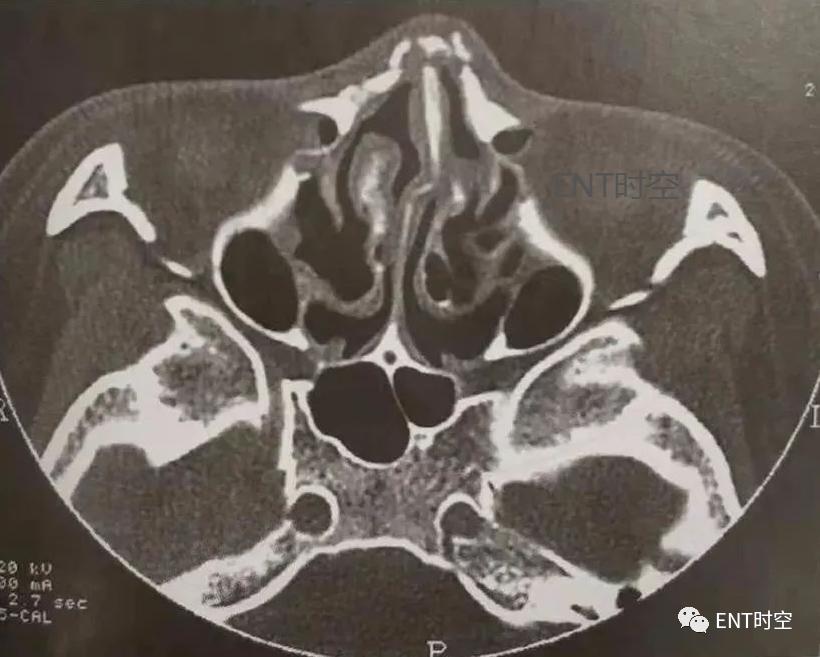

3、筛窦骨折:筛窦位于筛骨蜂房结构中,骨壁菲薄,筛骨纸板构成眶内壁,筛板构成前颅窝底,介于鼻腔顶和筛窦之间。单纯筛窦骨折少见,多为复合性骨折。(图1、2)

图1鼻-鼻窦多发骨折。轴位CT显示鼻骨、右侧上颌骨额突、鼻中隔及眶外侧壁骨折。

图2鼻-鼻窦多发骨折,轴位CT示上颌窦各壁及翼突多发骨折,上颌窦内积血。